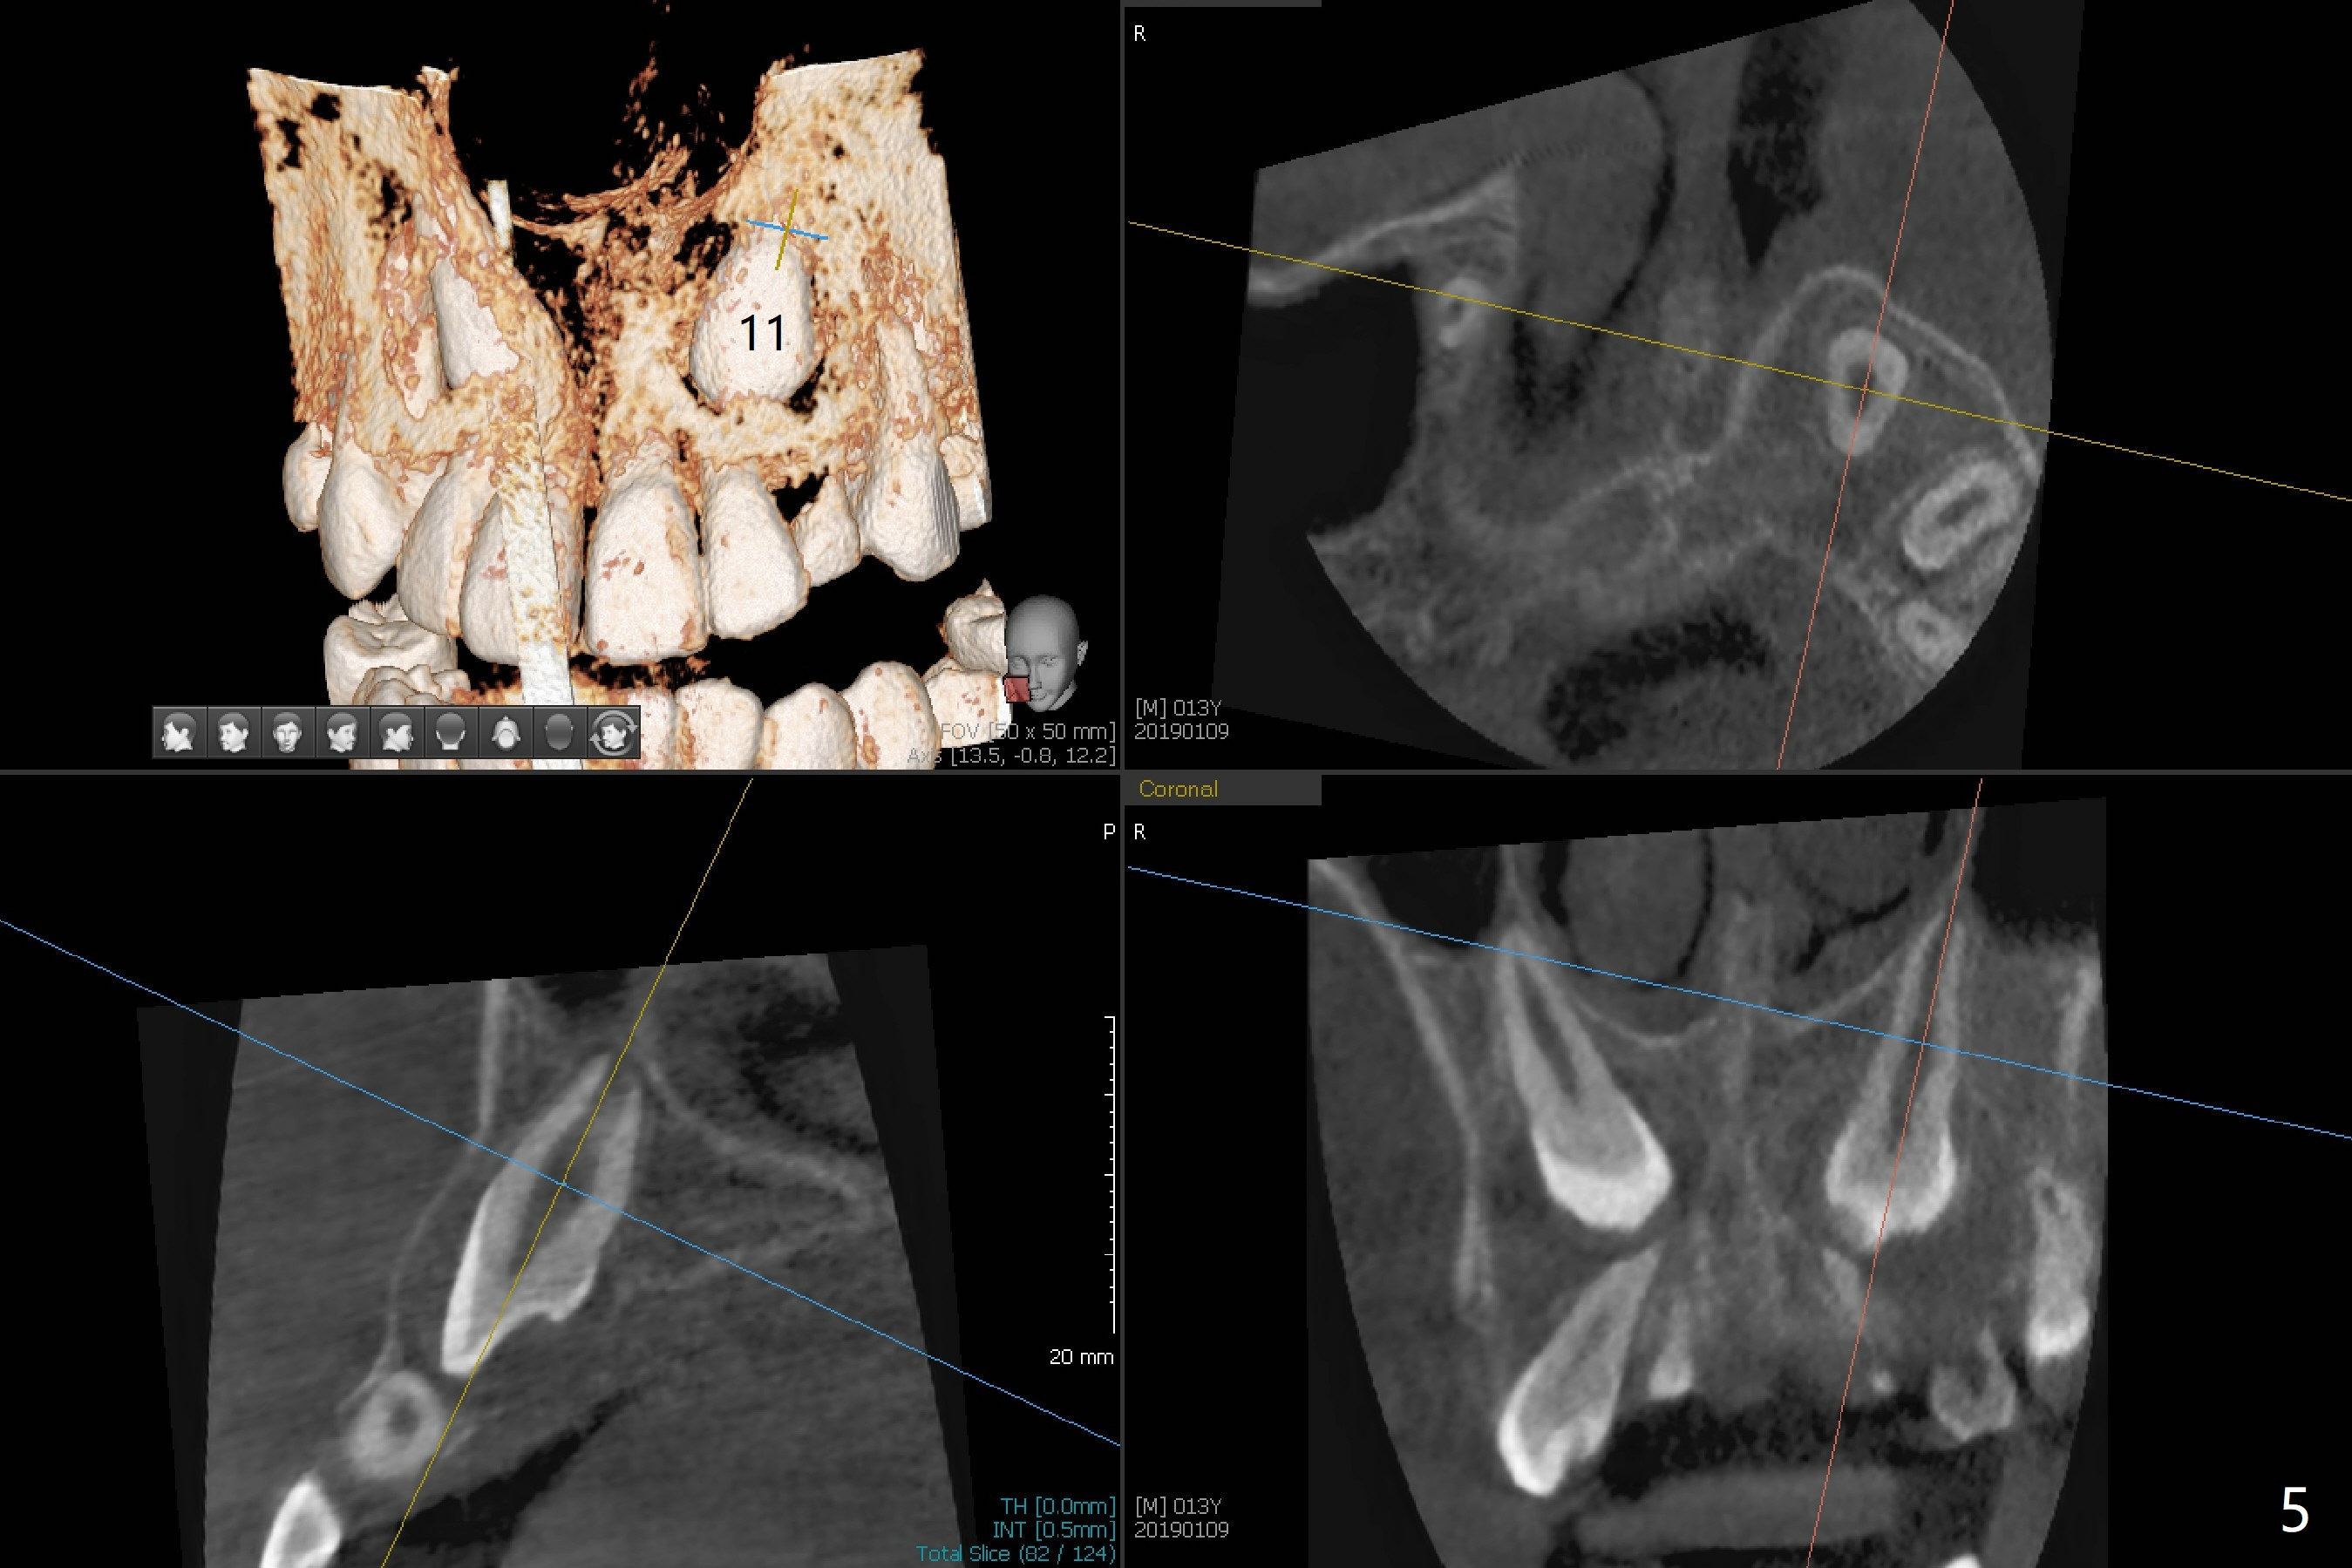

A 13-year-old boy with Class III malocclusion returns with mother from an orthodontic office for extraction of the tooth H with panoramic X-ray taken last year (Fig.1). An interesting finding was present, but not diagnosed a year earlier (Fig.2).

A cystic lesion around each of the impacted permanent upper canines. A normal dental sac or dentigerous cyst?